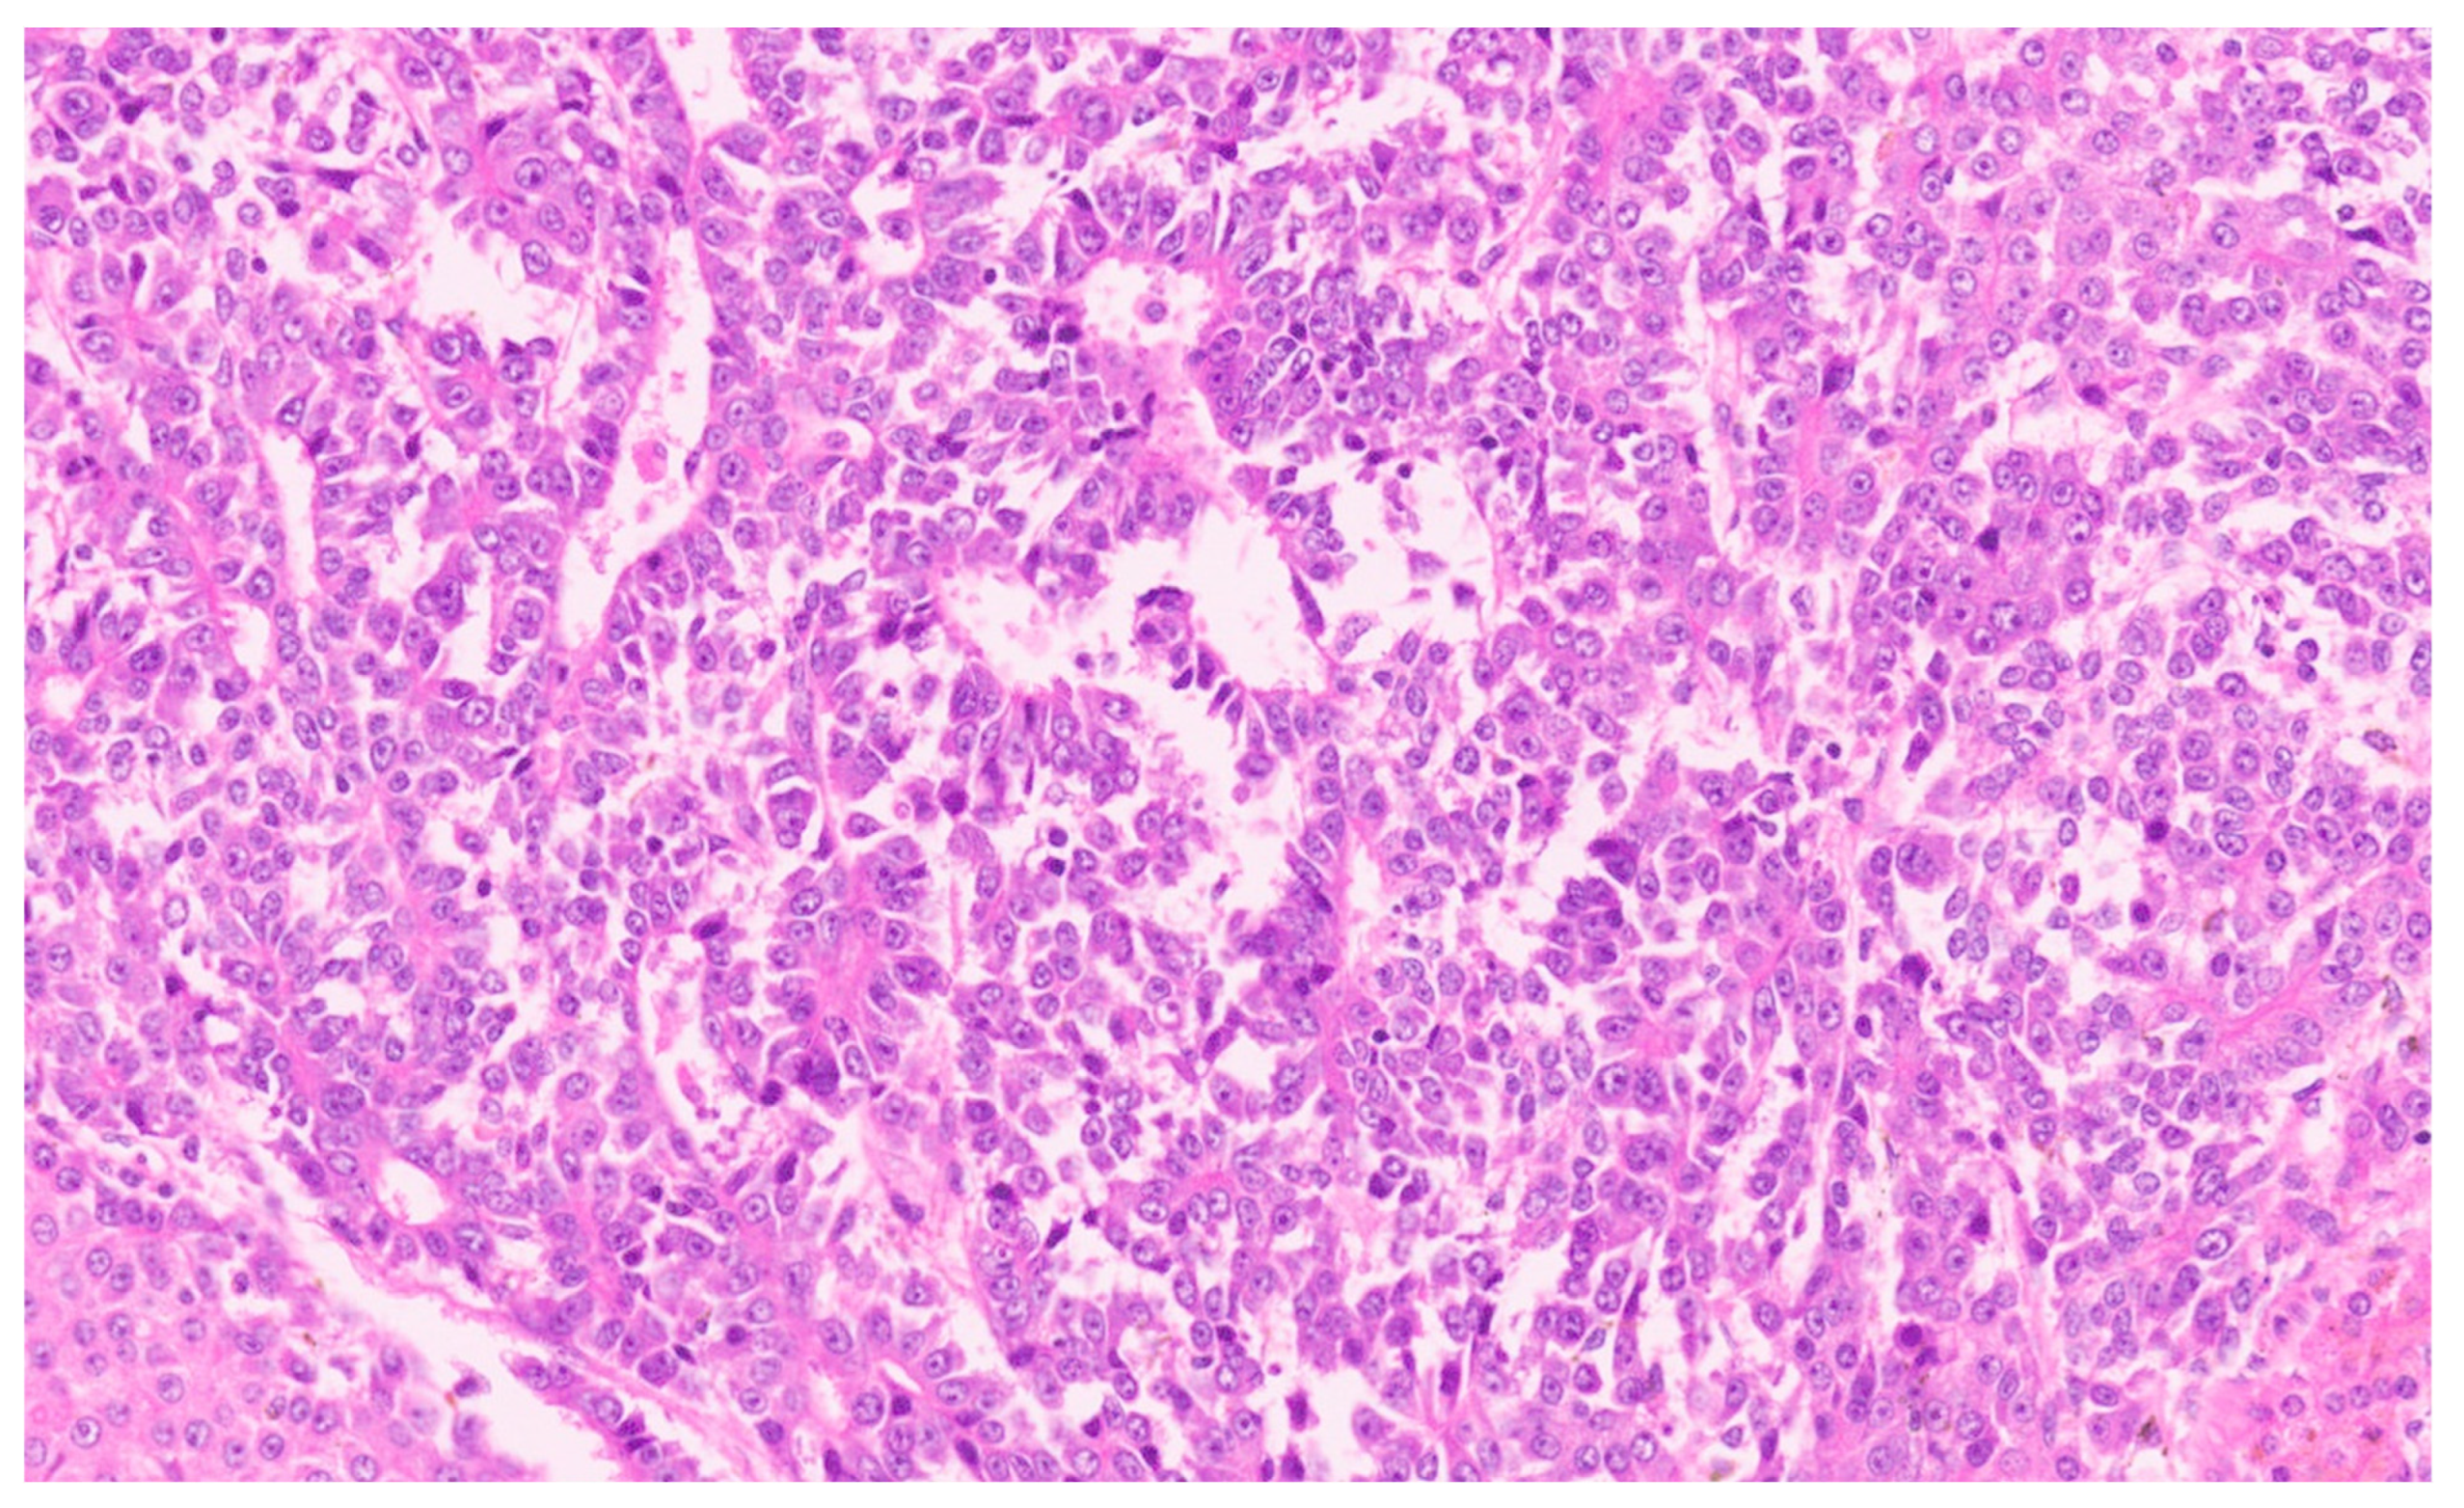

16.3. Pathology

| Histopathology | Well Differentiated | Moderately Differentiated | Poorly Differentiated |

|---|---|---|---|

| Arrangement | Trabeculae that are at least 3 cells thick and lined by sinusoids, pseudoacinar arrangement | Trabeculae that are 15–20 cells thick lined by sinusoids, pseudoacinar arrangement | Sheets or nests of cells not resembling hepatocytes. |

| Cells and nuclei | Resemble hepatocytes with mild nuclear pleomorphism, centrally placed round nuclei, and abundant cytoplasm | Moderate nuclear pleomorphism, large nuclei with prominent nucleoli and intranuclear inclusions, abundant cytoplasm. | High N/C ratio, nuclear pleomorphism, prominent nucleoli and intranuclear inclusions, numerous mitosis |

| Necrosis | Usually absent | May be seen | Present |

| Immunohistochemistry | Variable glypican 3 and glutamine synthetase levels. Negative for β-catenin nuclear staining | Glypican 3 and glutamine synthetase are positive in 50% of cases, β-catenin is variable | Glypican 3 and glutamine synthetase |